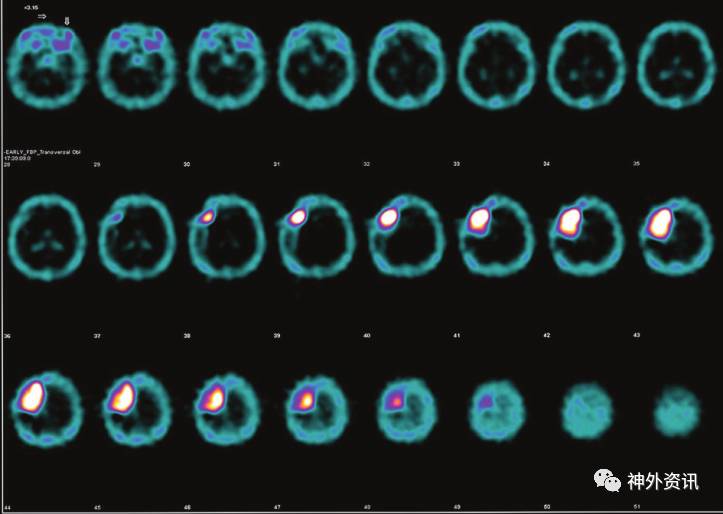

采用高级MRI技术进行常规扫描的同时,对该患者使用锝99m标记的SPECT检查。脑SPECT显示放射性药物均匀吸收,标准化摄取值(SUV)很高,支持脑膜瘤的诊断(图3)。

图3. 脑SPECT(Tc99m标记)轴位图像示:标准化摄取值(SUV)高。